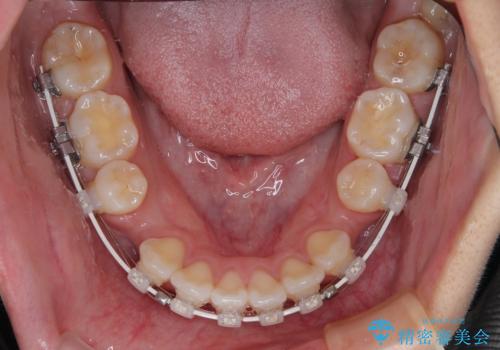

- 矯正装置

- 審美装置

- 前歯が突出して、眠るときに口が開いてしまうことを気にして来院された患者様です。

横から見た際の口元の飛び出した印象も改善したいとのことで、上下左右の第一小臼歯4本を抜歯し、ワイヤー装置にて抜歯矯正を行うこととしました。

舌の突出癖改善のためのトレーニングをしっかりと実践してくださり、2年強の治療期間でしっかりと仕上げることができました。